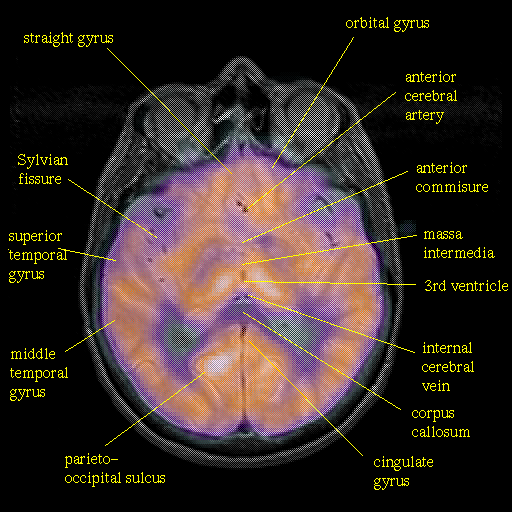

overlay : Slice 27

Slice 27

[Whole Brain Atlas Home Page] [Brain structure list] [Navigator Help Page]

Keith A. Johnson (keith@bwh.harvard.edu), J. Alex Becker (jabecker@mit.edu)